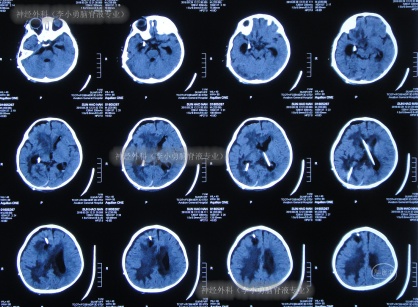

2018年1月23日(入院3天)接受了腰穿化验脑脊液提示细胞数增高,考虑是“化脓性脑膜炎”,2018年1月25日(入院后5天),查头MRI增强示脑内多发异常信号,考虑脑脓肿形成(图-1、图-2)。

图-1:2018年1月25日头部核磁增强

图-2:2018年1月25日头部核磁增强